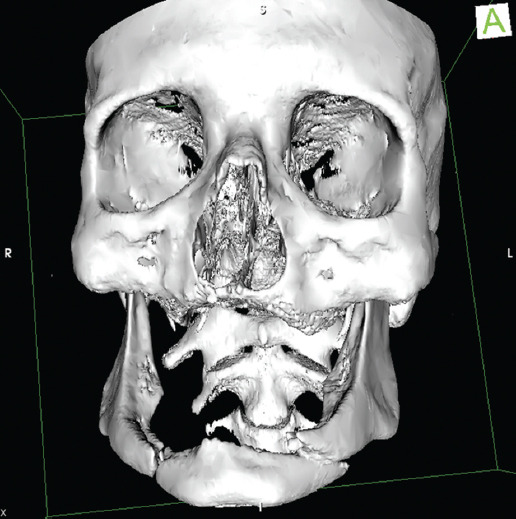

Históricamente se han tratado las fracturas en mandíbulas atróficas utilizando fijación intermaxilar, férulas de Gunning, alambrado local asociado a injertos costales, bioimplantes, etc.1,2. En las décadas de 1970 y 1980 se cambió el enfoque del tratamiento, utilizando placas de compresión dinámica3, y posteriormente placas no compresivas con tornillos bicorticales (Prein, 1993) con injerto óseo autólogo. En 1996, Luhr publicó la utilización de placas de compresión dinámica y la clasificación de atrofia mandibular de acuerdo a la altura4: clase I = 16-20 mm, clase II = 11-15 mm y clase III ≤ 10 mm (Figs. 1 a 3). A finales de la década de 1990 se recomendaron sistemas bloqueados o cerrojados ante los problemas de estabilidad y para preservar la biología ósea1.

Los 17 pacientes fueron tratados con osteosíntesis mediante placas y tornillos. El estudio de tomografía computarizada (TC) de cortes finos (1 mm) mostró en el preoperatorio la altura mandibular en el sitio de la fractura y la deficiencia de hueso esponjoso en los bordes de la fractura, orientando sobre si utilizar injerto óseo. Los injertos óseos, que tienen como finalidad mejorar la respuesta osteogénica en el lugar de la fractura, se tomaron del tercio proximal de la tibia para disminuir la morbilidad del área donadora que tiene la cresta iliaca. Los pacientes a quienes se aplicó injerto óseo presentaban atrofias de clase II y III de la clasificación de Luhr.

Utilizar la clasificación de Luhr es útil, ya que puede servir como guía para determinar el tipo de material y la posible necesidad de injerto óseo, aunada al uso de TC preoperatoria.